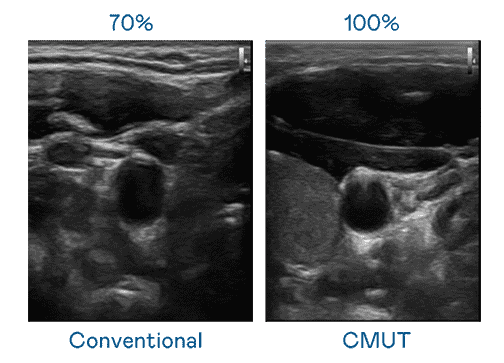

CMUT 技术是一种用电容式微机电元件来产生超音波讯号的技术。。。与传统 PZT 压电式技术相比,,,CMUT 频宽增加 30%,,,更宽频的超音波讯号让影像解析度大幅提升,,是实现高影像品质医疗超音波扫描、、、、促进精准医疗发展的关键技术。。。

超音波影像的解析度高低,,首先取决于探头能发出的讯号频宽。。冰球突破 CMUT 可提供高清晰的超音波讯号,,,提供高频宽、、、、高灵敏度、、、影像纹理细节更高的超音波影像,,协助医护人员缩短影像判读时间及利用精准的医疗影像进行诊断。。。。